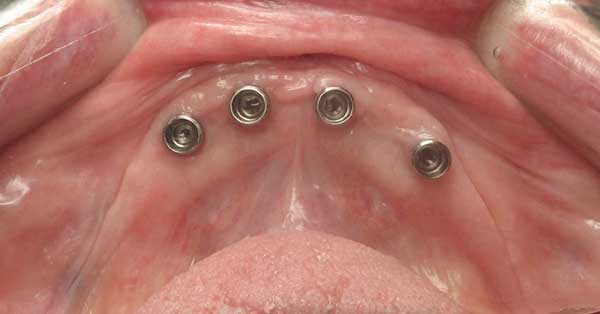

Gloria D.

This patient had been unhappy with her loose lower denture.  Placed four Implants to secure lower denture and she is now happy to report back that she can eat steak!